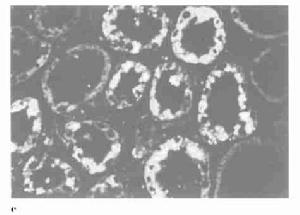

3.電子計算機斷層掃描或磁共振顯像:

可顯示腎實質缺血壞死特徵性改變,是特異性較高的無創性檢查方法。